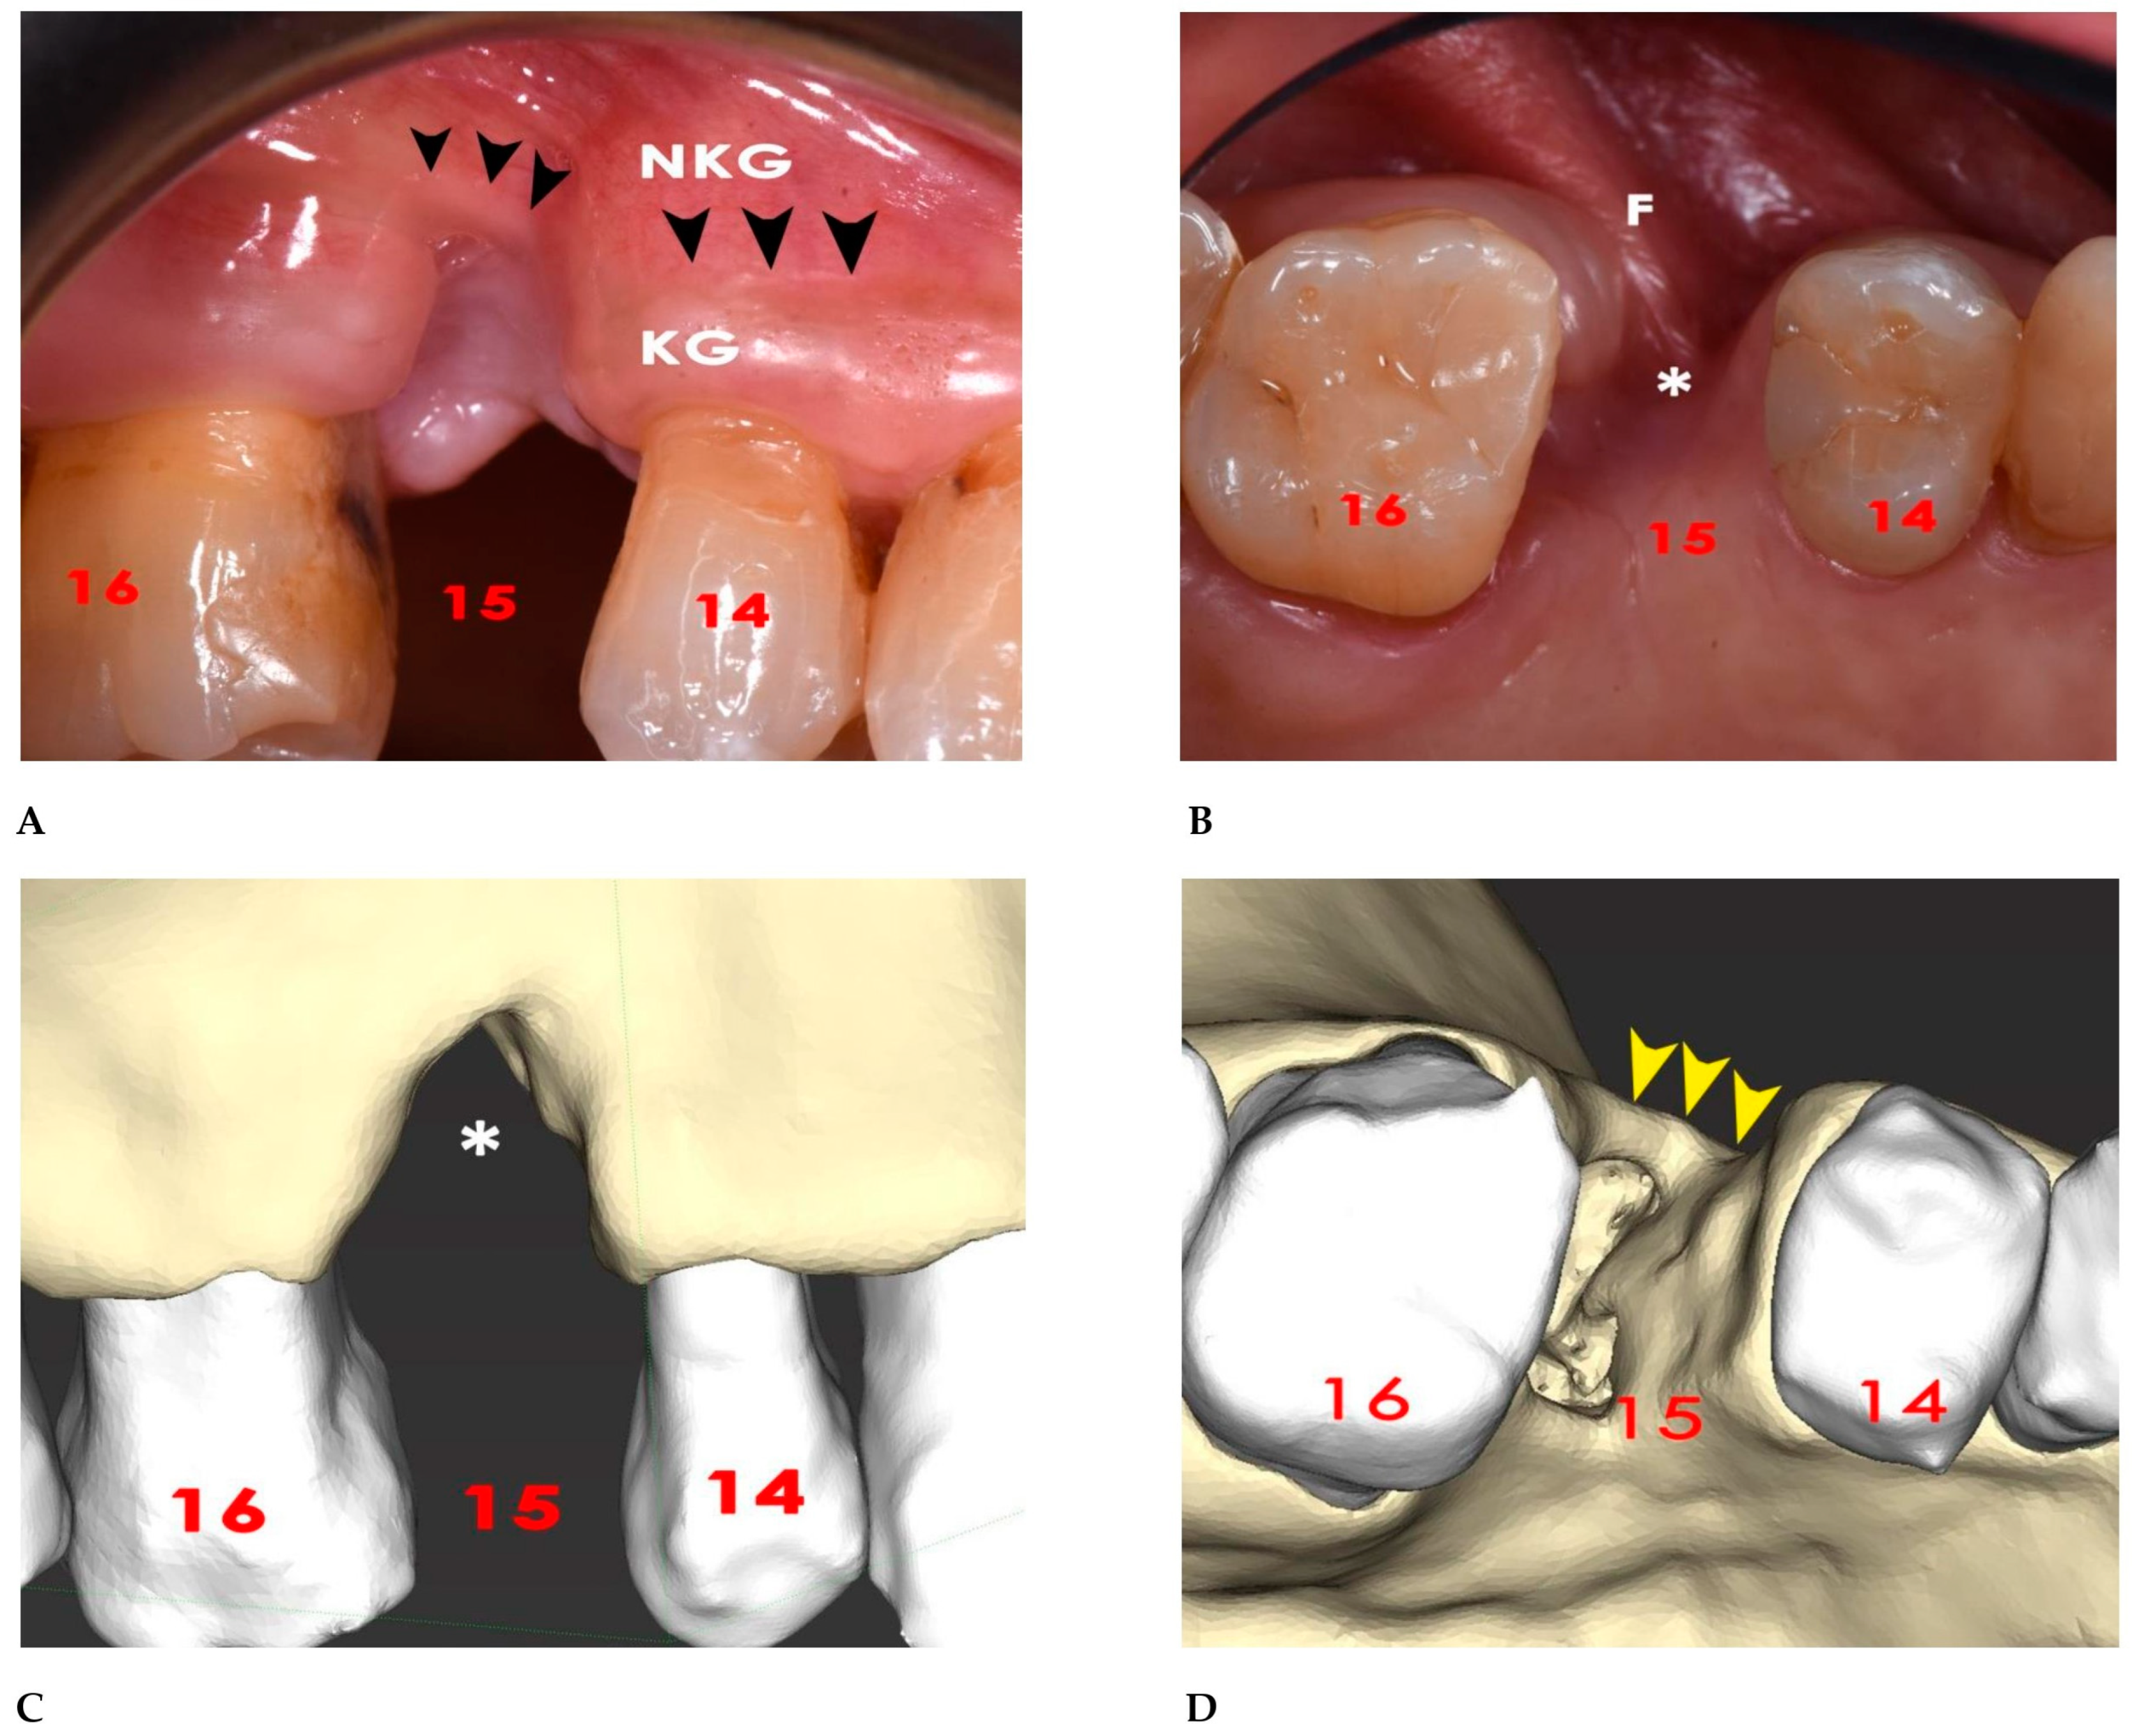

2.1. Surgical Simulation

2.2. GBR Simulation and Mesh Design